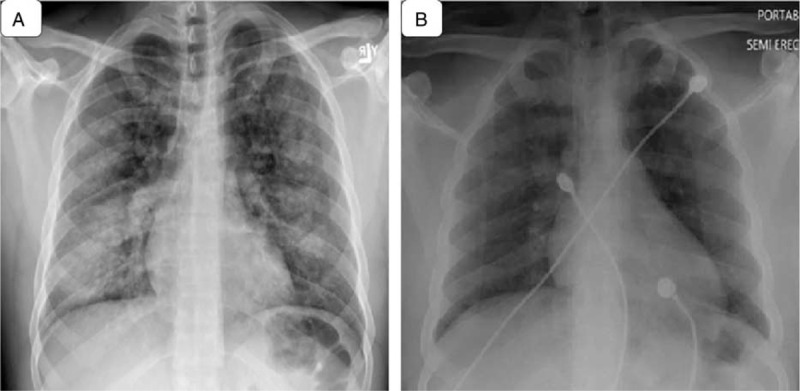

Chest radiograph (Figure 1A) showed increased interstitial markings and chest computed tomography (CT) scans (Figures 2 and 3) showed diffuse ground-glass opacities. An echocardiogram indicated a normal ejection fraction of 66% with no valvular abnormalities. A bronchoscopy with bronchoalveolar lavage (BAL) was initially bloody, but subsequently became clear (Figure 4). BAL cell counts showed leukocytes at 120 cells/mm3, with 98% neutrophils, and red blood cells at 28,250 × 106 cells/mm3. A transbronchial biopsy revealed chronic inflammation. The hemoglobin was 15.8 g/dl, coagulation profile was normal, vasculitis work up consisting of antinuclear antibody, rheumatoid factor, anti-DNA antibody, and antiglomerular basement membrane antibody was negative. The patient’s beta natriuretic peptide was 13 pg/ml and his urine toxicology was positive for cannabinoids.

The patient received a dose of furosemide and antibiotics were discontinued as the cultures were negative. Subsequently, his hemoptysis, cough, and shortness of breath resolved and was discharged home with follow-up in the pulmonary clinic. The patient’s chest radiograph before discharge demonstrated complete resolution of infiltrates (Figure 1B). This case is a unique case of hemoptysis likely due to marijuana inhalation, as no other possible causes were identified.